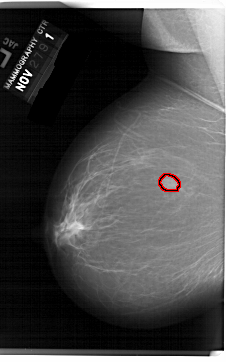

A_1519_1.RIGHT_CC

RIGHT_CC LINES 6316 PIXELS_PER_LINE 3886 BITS_PER_PIXEL 12 RESOLUTION 43.5 NON_OVERLAY

FILE: A_1519_1.LEFT_MLO.OVERLAY

TOTAL_ABNORMALITIES 1

ABNORMALITY 1

LESION_TYPE MASS SHAPE OVAL MARGINS OBSCURED

ASSESSMENT 4

SUBTLETY 5

PATHOLOGY BENIGN

TOTAL_OUTLINES 1

BOUNDARY